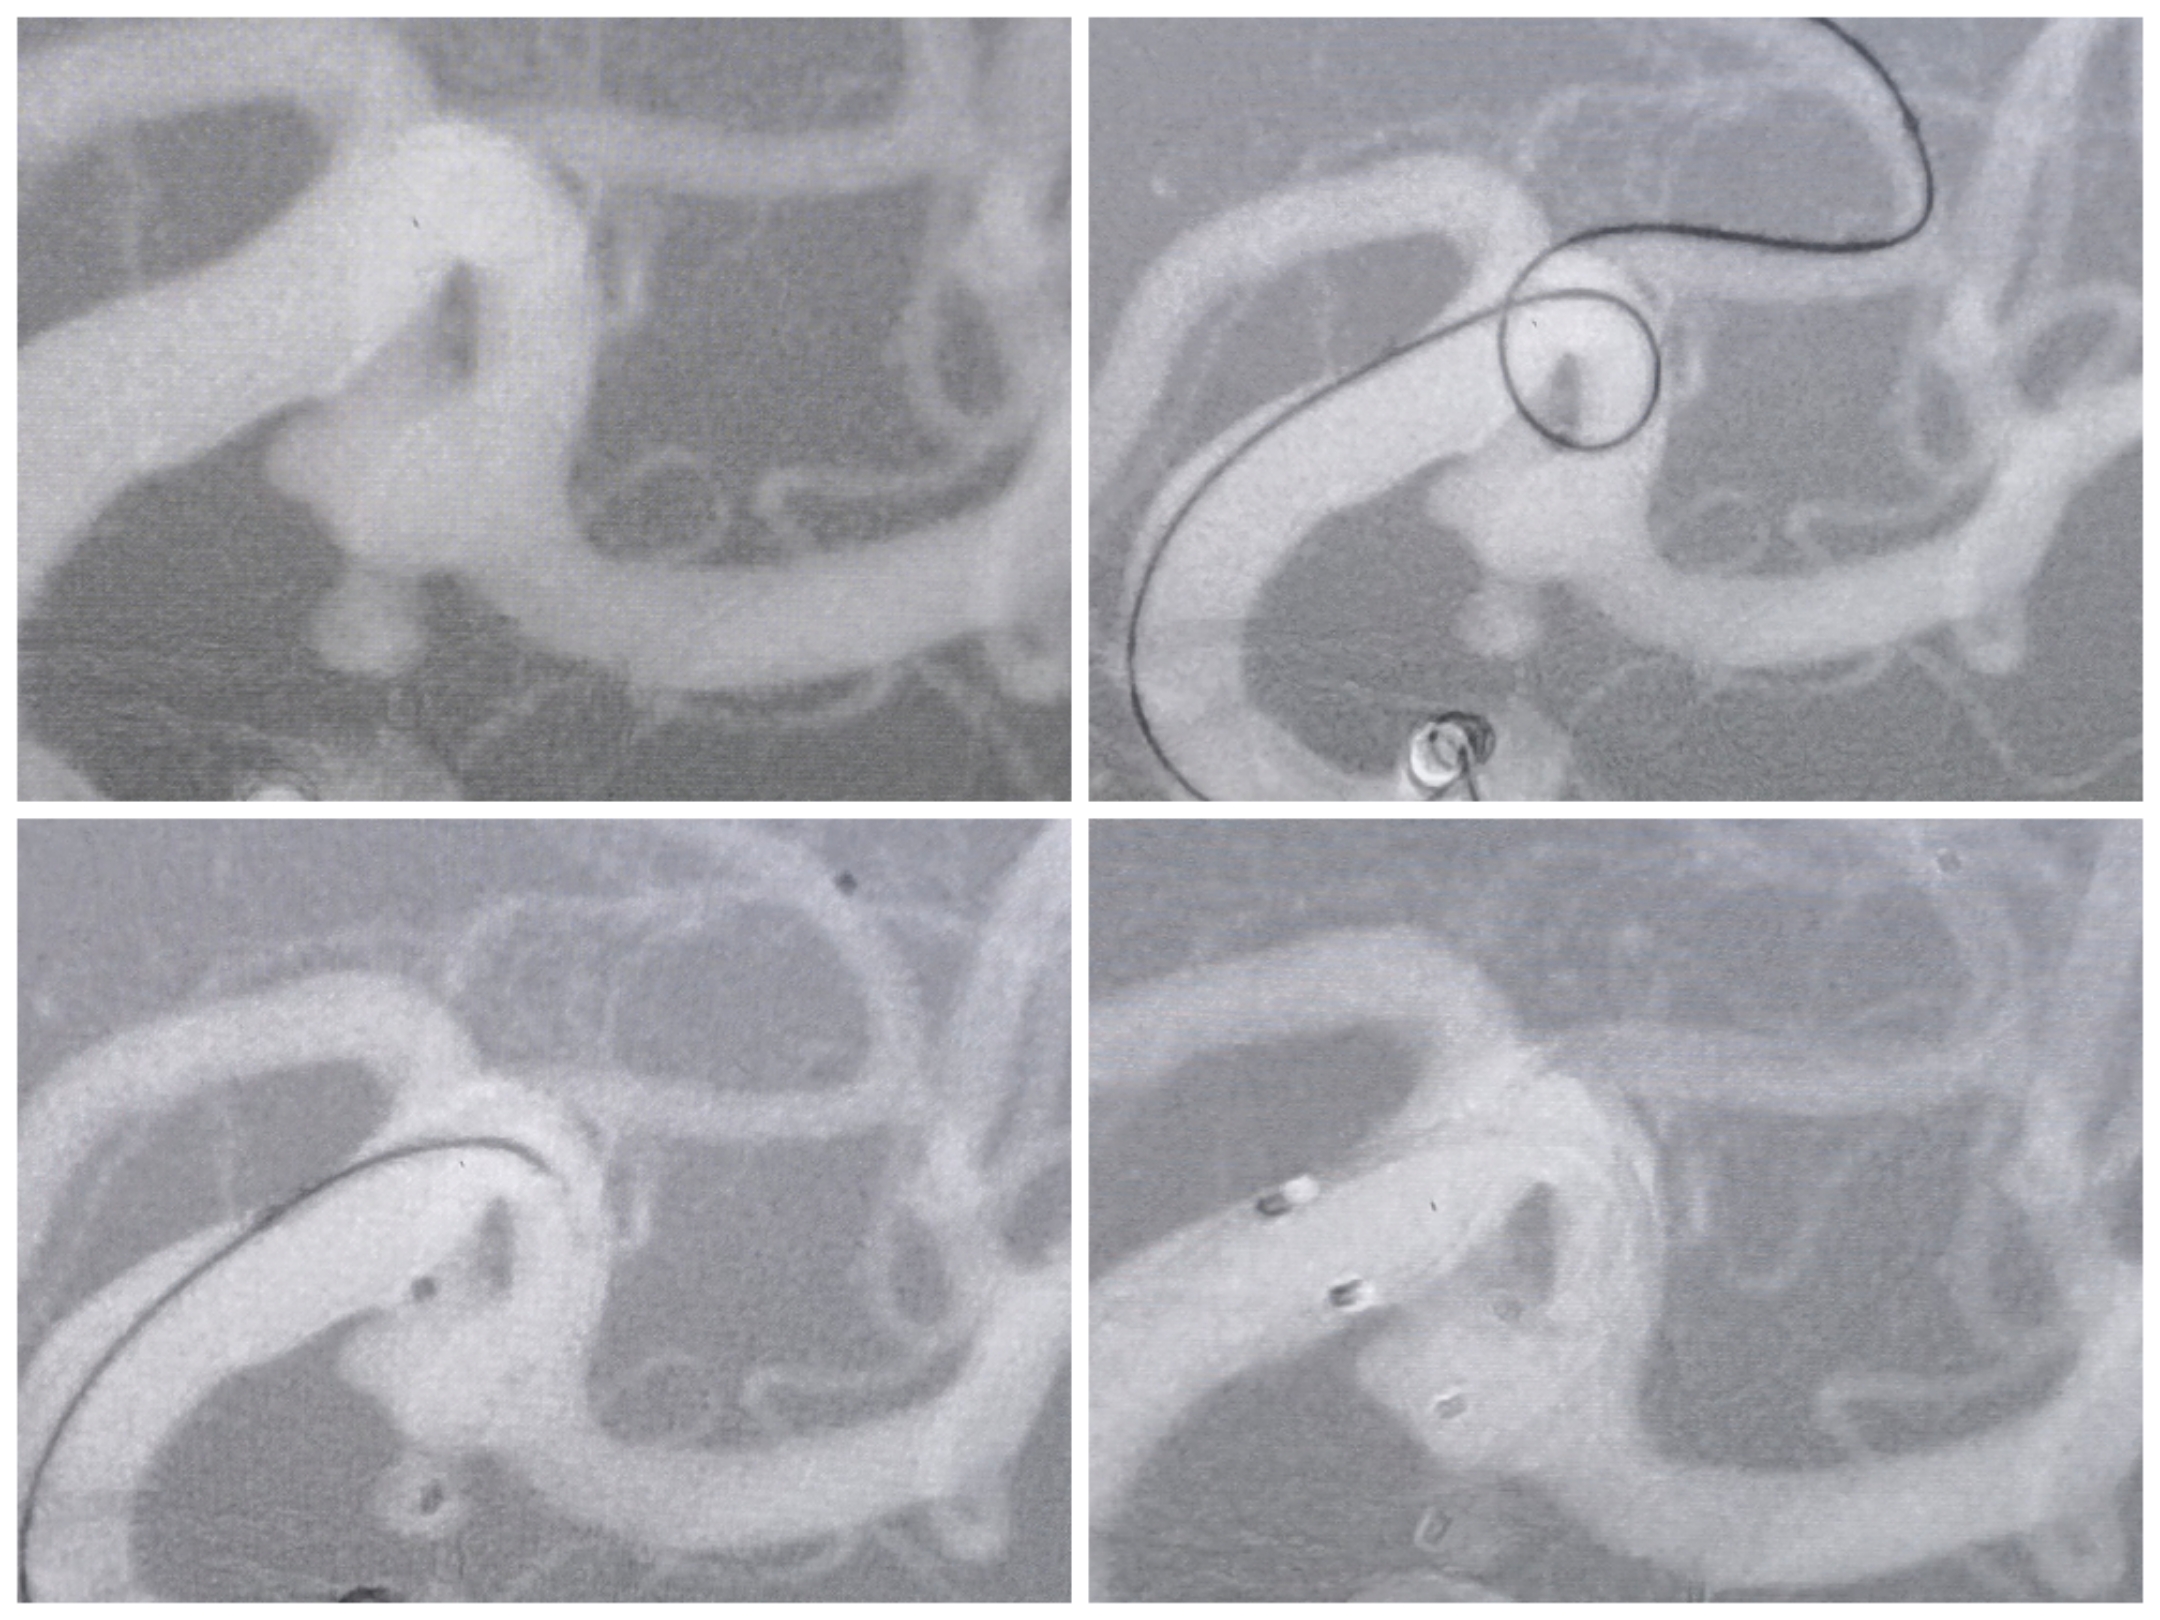

手术过程微导管布局情况:三系统栓塞,支架导管置于上干,两条微导管分别置于主囊和子囊中。

手术过程:先栓塞子囊,释放Atlas支架后甩尾(头端置于上干、尾端甩尾释放于下干开口保护两个干),后栓塞主囊

栓塞术后情况:支架甩尾保护双干,子囊及主囊栓塞完全